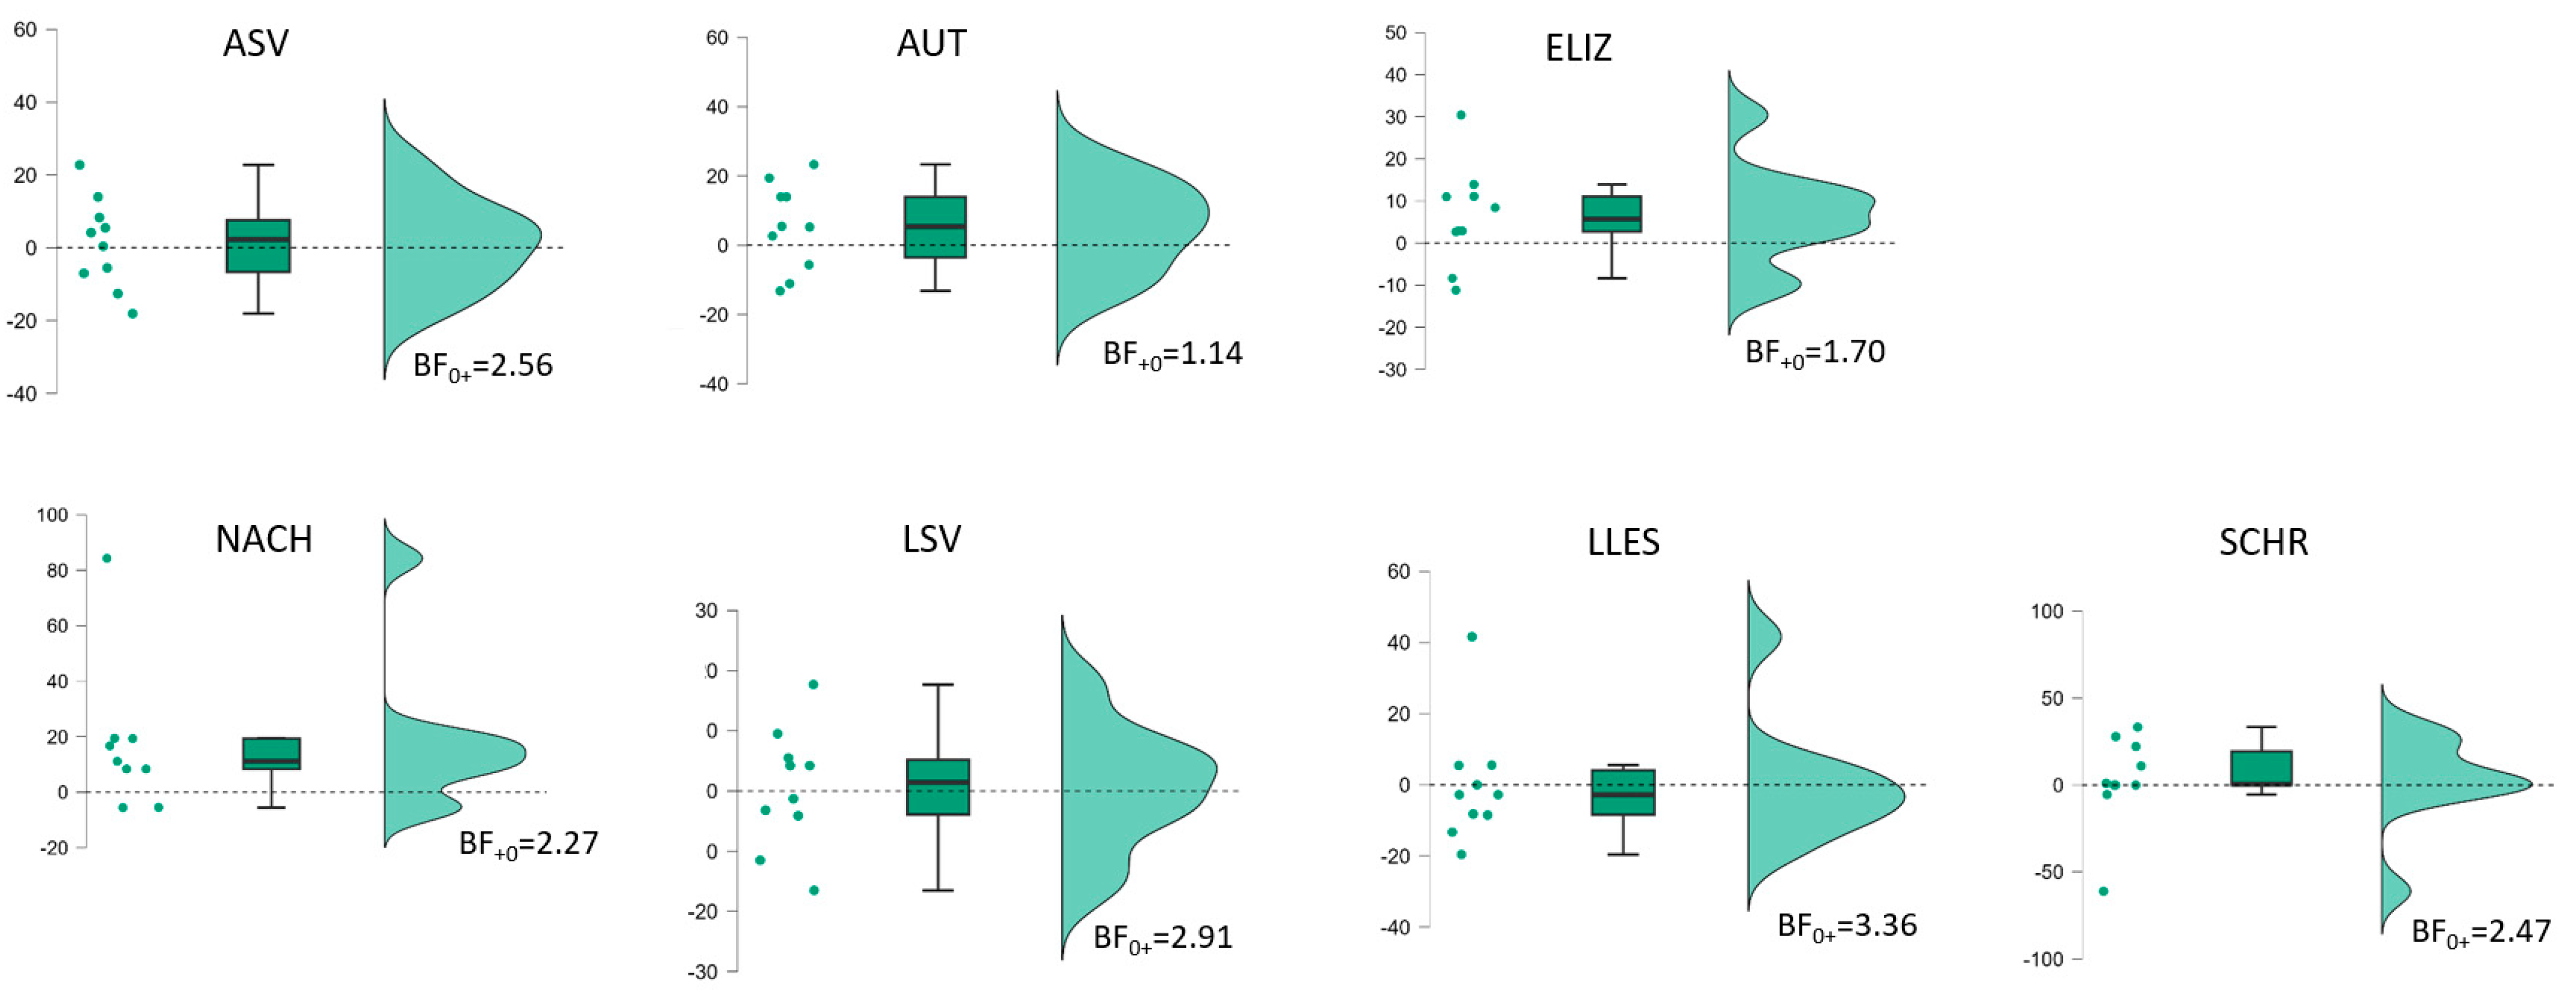

| B | Period 1 | Period 2 | Period 2−1 | Period 1 + 2 | ||||||||

| BIAS (n = 10) | t(9) * (p-v.) | Cohen d [95%-CI] | Bayes Factor | t(9) * (p-v.) | Cohen d [95%-CI] | Bayes Factor | t(9) * (p-v.) | Cohen d [95%-CI] | Bayes Factor | t(9) * (p-v.) | Cohen d [95%-CI] | Bayes Factor |

| Profile | 4.06 (0.001) | 1.29 [0.55–∞] | BF+0 34 | 6.80 (<0.001) | 2.15 [1.15–∞] | BF+0 700 | 2.22 (0.027) | 0.70 [0.10–∞] | BF+0 3.20 | 6.26 (<0.001) | 1.98 [1.03–∞] | BF+0 410 |

| ASV | 1.69 (0.063) | 0.54 [−0.04–∞] | BF+0 1.65 | 3.68 (0.003) | 1.16 [0.46–∞] | BF+0 21 | 0.31 (0.38) | 0.10 [−0.43–∞] | BF0+ 2.56 | 3.52 (0.003) | 1.11 [0.42–∞] | BF+0 17 |

| AUT | 3.26 (0.005) | 10.03 [0.36–∞] | BF+0 12 | 5.46 (<0.001) | 1.73 [0.50–∞] | BF+0 176 | 1.37 (0.102) | 0.43 [−0.12–∞] | BF+0 1.14 | 6.21 (<0.001) | 1.96 [1.02–∞] | BF+0 390 |

| ELIZ | 0.23 (0.41) | 0.07 [−0.45–∞] | BF0+ 2.71 | 2.49 (0.017) | 0.79 [0.11–∞] | BF+0 4.59 | 1.71 (0.060) | 0.54 [−0.0–∞] | BF+0 1.70 | 2.04 (0.036) | 0.65 [0.05–∞] | BF+0 2.56 |

| NACH (n = 9) | 4.14 (0.002) | 10.38 [0.57–∞] | BF+0 31 | 3.09 (0.007) | 1.03 [0.32–∞] | BF+0 9.19 | 1.94 (0.044) | 0.65 [0.02–∞ | BF+0 2.91 | 4.34 (0.001) | 1.45 [0.62–∞] | BF+0 39 |

| LSV | 2.84 (0.010) | 0.90 [0.26–∞] | BF+0 7.23 | 2.75 (0.011) | 0.87 [0.23–∞] | BF+0 6.40 | 0.14 (0.45) | 0.04 [−0.48–∞] | BF0+ 3.36 | 4.63 (<0.001) | 1.46 [0.67–∞] | BF+0 68 |

| LLES | 3.36 (0.004) | 10.06 [0.38–∞] | BF+0 14 | 1.61 (0.072) | 0.51 [−0.06–∞] | BF+0 1.49 | −0.05 (0.52) | −0.02 [−0.54–∞] | BF0+ 2.56 | 2.78 (0.011) | 0.88 [0.24–∞] | BF+0 6.65 |

| SCHR | 1.38 (0.100) | 0.44 [−0.12–∞] | BF+0 1.15 | 2.81 (0.010) | 0.89 [0.25–∞] | BF+0 6.92 | 0.35 (0.37) | 0.11 [−0.42–∞] | BF0+ 2.47 | 3.30 (0.005) | 1.04 [0.37–∞] | BF+0 13 |